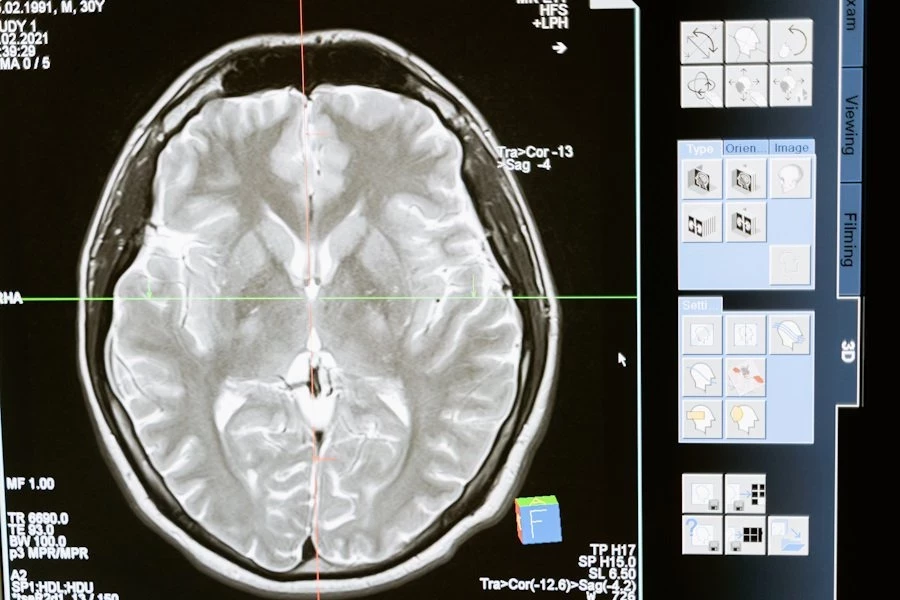

В Санкт-Петербургском политехническом университете создана компьютерная программа SpineTool. Эта программа предназначена для автоматического анализа изображений мозга и определения формы отростков нейронов, которые называются дендритными шипиками, пишут «Известия».

SpineTool шаг за шагом анализирует эти изображения и строит трехмерную модель дендритных шипиков. При этом каждый шипик уникален, и нет двух одинаковых по форме. Раньше ученые использовали числовые параметры, такие как длина, ширина и объем, чтобы описать шипики. Но это давало только абстрактное представление об их структуре. Российские специалисты впервые выделили отдельные сегменты в изображении шипиков и на основе этих сегментов построили столбчатую диаграмму, которая называется гистограммой.

Таким образом, SpineTool позволяет более точно и качественно исследовать форму дендритных шипиков, что дает ученым новые инструменты для изучения функционирования мозга и поиска лекарственных средств против нейродегенеративных заболеваний.